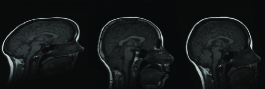

Figure 7: Resulting registration of images with random affine warps. Each row includes source, target and registered source

Refer to caption

In Figure 7, three example registration results of randomly and affinely warped images are shown. The resulting images clearly show that registered source images are in good agreement with target images. Registration quality is measured over 30 randomly deformed images by mean of the square of the differences in intensity (MSE). Experiment has been done both in image scale and on standard scale to show improvement in MSE sense. Table-1 shows the MSE, maximum MSE and minimum MSE over 30 registration examples on image scale and on intensity scale respectively.